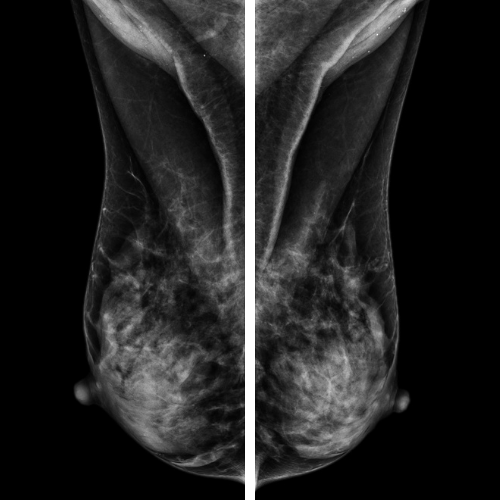

Alışılagelmiş mamografiden farkı görüntülerin bilgisayarlı dijital teknoloji ile elde edilmesidir.

ACRIN DMIST çalışması yoğun meme dokusu olan kadınlarda digital teknolojinin faydalarını göstermiştir .